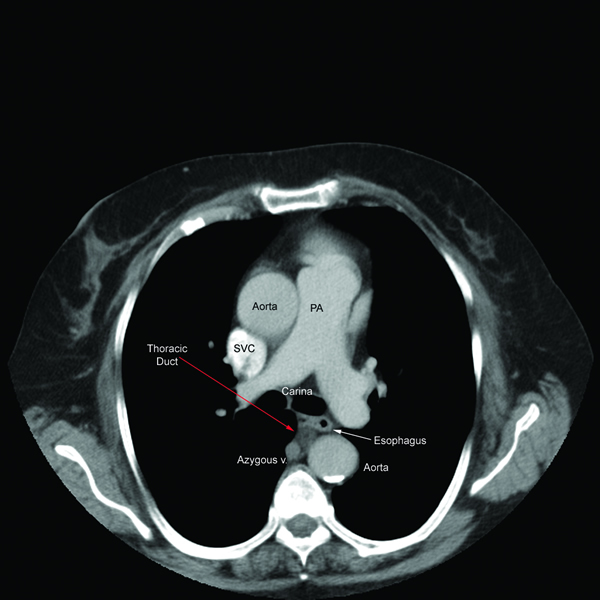

Exploration of this area bluntly will reveal the thoracic duct as a thin tubular structure with occasional peristalsis (Video 5). Once a sufficient length of duct is isolated it is doubly clipped using 5 or 10mm clips depending on the size of the duct and is divided (Figures 4-6). Transection with a linear cutting stapler with a vascular load (30mm length, 2.0mm staple height) works just as well (Video 6). The stapler or clip applier can be introduced through the working incision or the incision used for retraction of the diaphragm. If an adequate length of the duct can be isolated, a portion can be excised and sent for frozen section to confirm its identity.

| Figure 4: Thoracic Duct isolation. | Figure 5: Thoracic Duct Ligation. | Figure 6: Thoracic Duct Divided. |